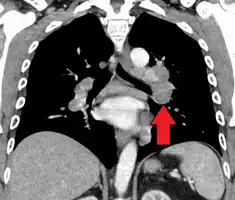

Hilar adenopathy especially on the person's left (AP CXR) -

Hilar adenopathy especially on the person's left (coronal CT) -